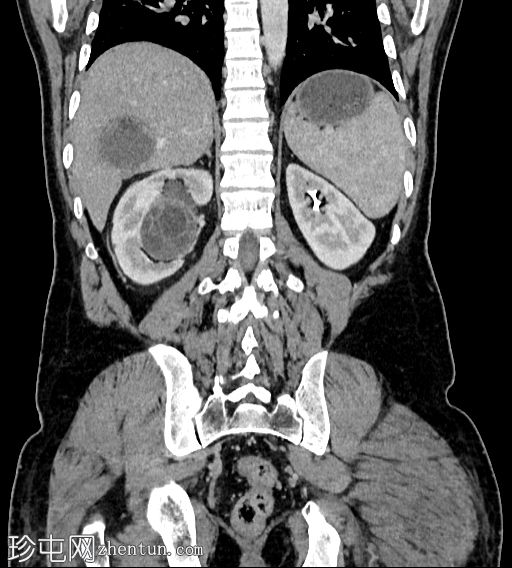

轴位增强扫描(门静脉期)

2.png

肝脏VII段可见一边界清晰的囊性病变,内部有分隔,囊壁可见钙化。

右肾中央部分(肾门)可见一囊性病变,中心可见基质,周围可见子囊。该病变与肾盂肾盏无交通。病变周围可见两处高密度影,位于上、中肾盏,无法区分是结石还是病变壁钙化。另可见上极肾盏中度扩张。